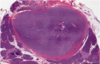

psomma body

papillary carcinoma

Psammoma body: calcified structures (tumor cell necrosis)